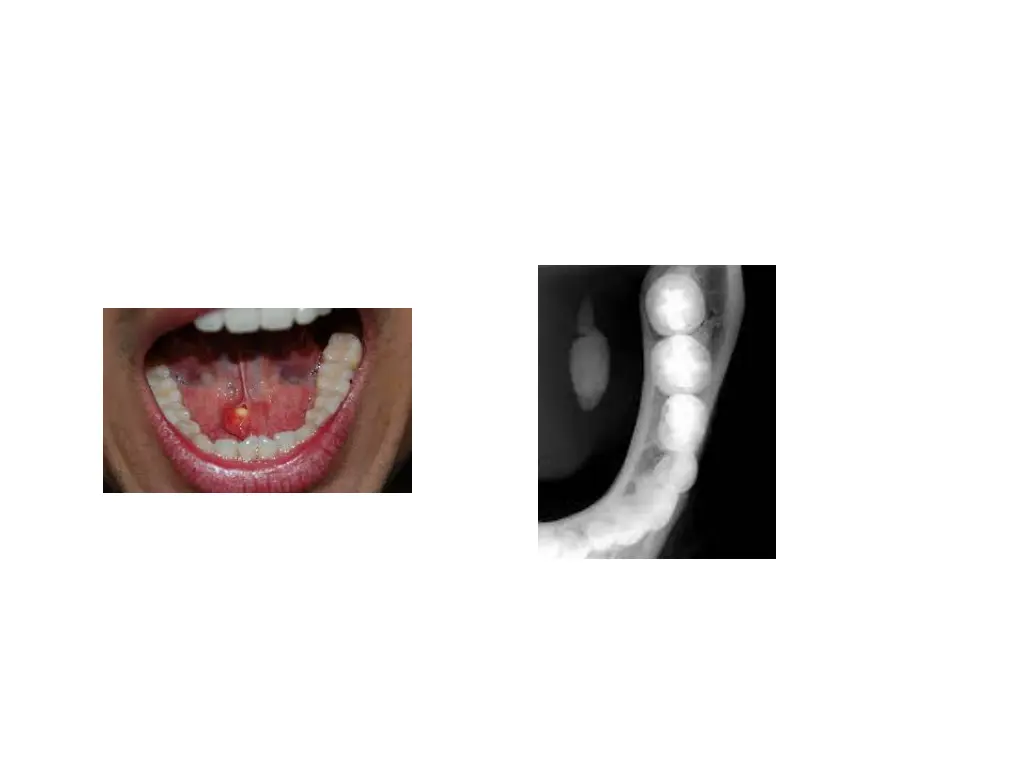

Mucoceles Is a clinical term that describes swelling caused by accumulation of saliva at site of traumatized or obstructed minor salivary gland duct Classified as extravasation and retention types A large form of mucocele located in floor of mouth is known as ranula

Mucocele Extravasation mucocele: results from trauma to minor glands. Laceration leads to pooling of saliva in adjacent submucosal tissue and consequent swelling Retention mucocele: due to obstruction of minor salivary gland duct by calculus or due to contraction of scar tissue around injured minor salivary gland duct Blockage causes accumulation of saliva and dilation of duct Eventually, an aneurysm like lesion forms, which can be lined by ept of dilated duct

Clinical presentation Extravasation type most frequently occur on lower lip, other regions being buccal mucosa, tongue, FOM,retromolar region Retention cyst: palate or FOM h/o trauma followed by development of lesion Present as discrete painless smooth surfaced swellings ranging from few mm to cm Superficial lesions always have a bluish hue Lesions size vary over time Pts frequently traumatize superficial one, allowing to drain and deflate In these circumstances, they recur

Treatment Surgical excision Removal of associated salivary glands is essential to prevent recurrence Surgical removal may traumatize adjacent glands Intralesional injections of corticosteroids have been successfully used